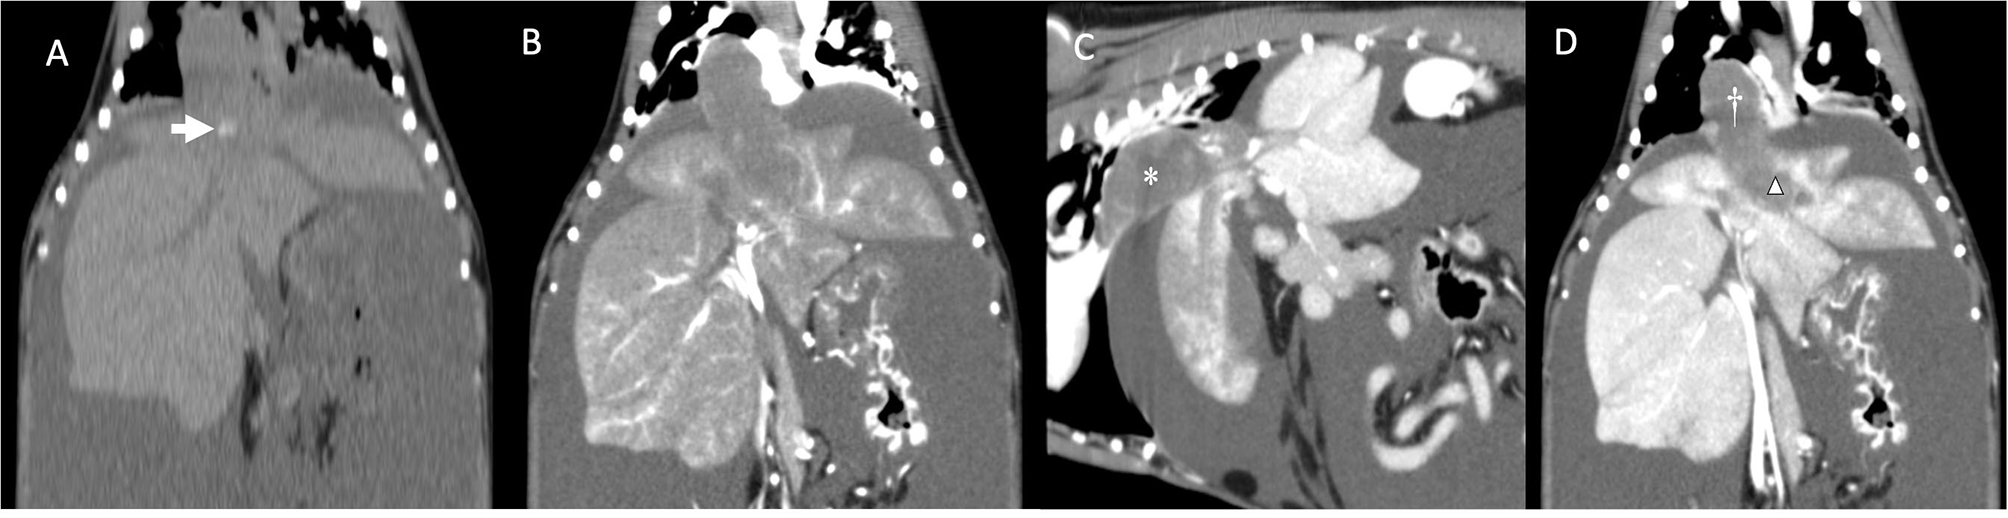

One month after the last appointment (9 weeks after the initial presentation), because of the persistent severe ascites requiring frequent abdominocentesis, the owner elected to have a computed tomography (CT) scan of the abdomen performed in preparation for surgical thrombectomy. The dog's physical examination was unchanged. CBC, serum biochemistry, and coagulation panel were repeated. The CBC showed an increase in the reticulocyte count. The serum biochemistry showed hypoproteinemia and hypoalbuminemia and a minimally increased ALT. Activated partial thromboplastin time and prothrombin time were normal. The dog was also blood-typed and was DEA 1.1-negative. Thoracic radiographs were obtained before surgery and showed a mild diffuse interstitial pattern throughout the pulmonary parenchyma, an enlarged caudal vena cava, and no evidence of metastatic disease. The dog was anesthetized, and a CT examination with an angiogram of the abdomen revealed the presence of a large amount of mixed soft tissue/mineral attenuating material in the caudal vena cava and left hepatic vein (Figure 2). The thrombus extended from the liver to the right atrium, with minimal contrast enhancement noted compared to the pre-contrast images. Patchy contrast enhancement of the left lateral, left medial, quadrate, and right medial liver lobes, a small conglomeration of vessels ventral to the azygos vein communicating with the portal circulation, caudal vena cava duplication at the level of the left renal vein, and marked abdominal effusion were also noted. A caudal vena cava thrombus with secondary hepatic congestion and ascites was prioritized with neoplasia being a less likely differential diagnosis. Two liters of serosanguinous fluid were drained from the abdominal cavity, while the dog was under general anesthesia in preparation for the thrombectomy the following day. The dog was prepared for surgery, and a combined median sternotomy and a midline laparotomy was performed to approach the vena caval lesion. Upon inspection of the vena cava, a hard intraluminal mass invading the vessel wall was palpated. Intraoperative fine-needle aspiration of the lesion was performed with a 25-g needle. Cytologic examination revealed clusters of cells with poorly distinct cytoplasmic margins and round to rarely ovoid nuclei with finely coarsely stippled chromatin. Some clusters of cells had a minimal amount of pink extracellular matrix. These findings were consistent with a neoplastic process, and a diagnosis of possibly neuroendocrine neoplasia was favored by the pathologist on duty.

Figure 2

(A) Dorsal reconstruction of dog's computed tomography before administration of contrast medium. Note the mineralization inside the mass/thrombus (arrow). (B) Dorsal reconstruction of dog's computed tomography (arterial phase). Note the minimal contrast enhancement compared to (A). (C) Sagittal reconstruction of dog's computed tomography showing a large mass/thrombus (asterisk) completely obstructing the caudal vena cava. (D) Dorsal reconstruction of the dog's CT showing the large mass/thrombus occupying the caudal vena cava (cross) and invading into the left hepatic vein (triangle). Note the patchy appearance of the congested left liver lobes. No parenchymal invasion of the mass is noted.

When the CT angiogram was performed, the mass was minimal-to-no contrast enhancing compared to the pre-contrast images. This is in accordance with what was noted in a case of chondroblastic osteosarcoma of the pulmonary artery (14), and this feature together with the lack of a primary lesion rules out the presence of a tumor thrombus. The poor vascularity of the mass in these two cases could explain the CT findings. On CT images, the focal marked dilation of the caudal vena cava and the presence of mineralization within the thrombus could have raised concerns for a primary intravascular neoplasia rather than a bland thrombus, even if cases of mineralized chronic bland thrombi, due to dystrophic mineralization, have been reported (20).